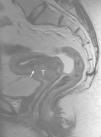

En este artículo revisamos los puntos clave indispensables para realizar una correcta estadificación del cáncer de cérvix mediante resonancia magnética.

ConclusiónLa resonancia magnética es el método de elección para la estadificación locorregional del cáncer de cérvix. Una correcta valoración de sus factores pronósticos, como el tamaño tumoral, la invasión de estructuras adyacentes y la presencia de metástasis ganglionares, resulta fundamental para decidir un adecuado manejo terapéutico.